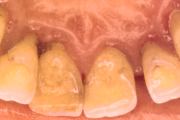

- igemed veritsevad (19)

- igemed punetavad (21)

- ige on paistes (mädapunn)

- igemed on tursunud/vohavad (17)

- igemepiir on taandunud (3)

- puudulik suuhügieen (5)

- igemepealne hambakivi (5)

- halb hingeõhk / suu haiseb (12)